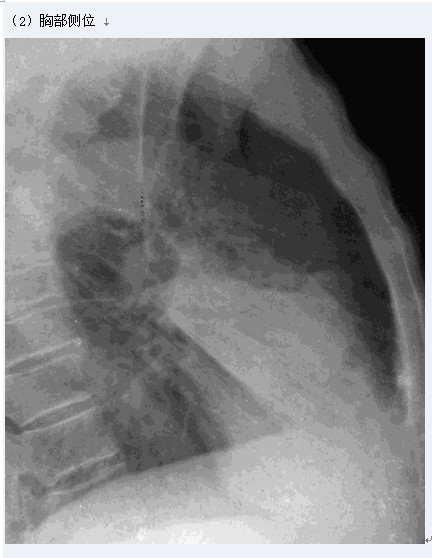

大葉性肺炎

圖示為右肺中葉大葉性肺炎